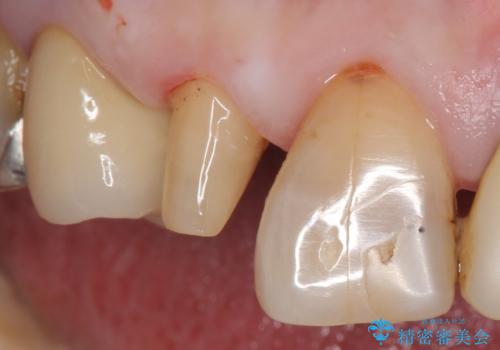

大きい虫歯で欠けた前歯 セラミッククラウンで治療

- 前歯が欠けたとのことで来院。

確認すると上の前歯の裏側に大きな虫歯がありました。

元々歯と歯の間のすき間が大きく食べ物が良く詰まるとのことでした。

クラウンでの修復は歯の形を変えある程度すき間を埋めることが可能です。